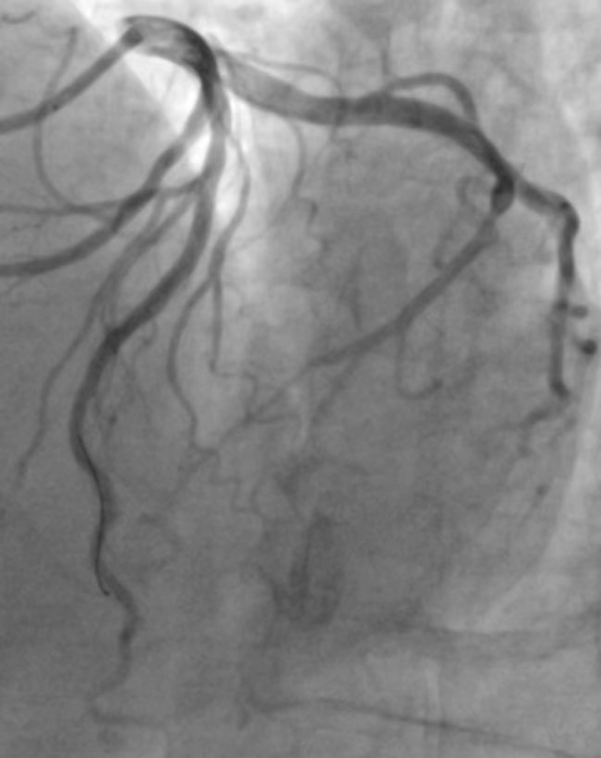

徐教授应用机器人将支架送至病变处,精准定位后植入2.75 * 38mm支架,随后使用3.0 * 15mm球囊进行后扩张,经多体位造影及IVUS检查确认,支架贴壁良好,支架内未见明显残余狭窄,远端血流TIMI 3级,病变处管腔面积增至5.87mm²。

支架置入后即刻造影图像